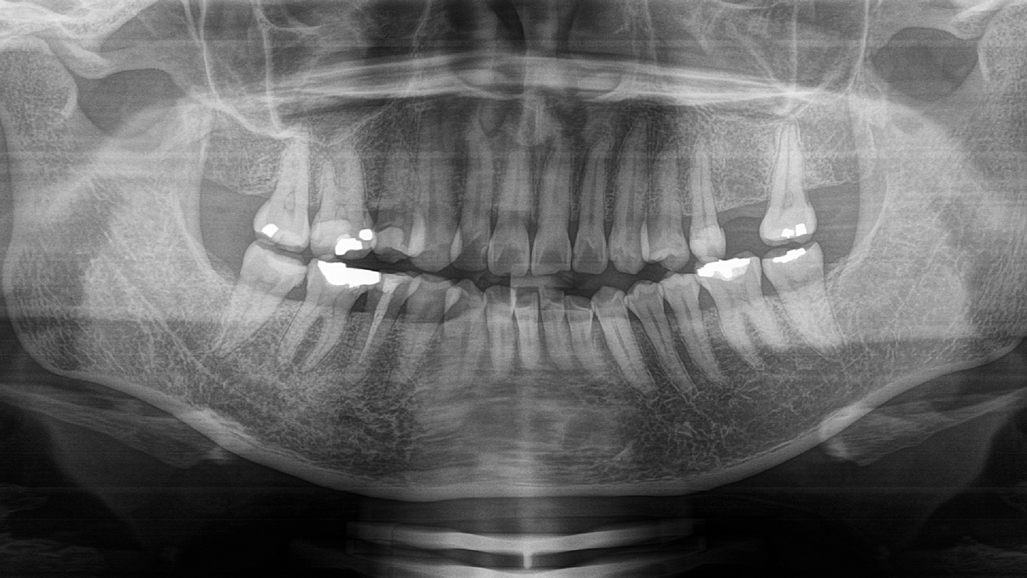

Tooth #46 was tender to percussion, non-tender to palpation and had no response to the electric pulp test and cold test. Analysis of the dental panoramic tomogram showed a large mesio-occlusal amalgam restoration with recurrent caries, reaching close to the mesial pulp horn of the tooth (Fig. 1). Two roots could be observed and no visible root resorption. Slight periodontal ligament widening was evident and a periapical lesion. She was diagnosed with irreversible pulpitis of tooth #46 and chronic periapical periodontitis.